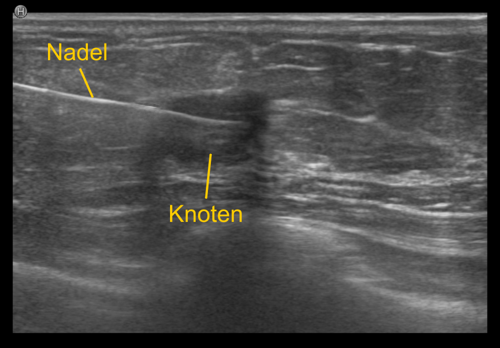

Bei der Gewebeprobeentnahme, der sogenannten 'Biopsie', wird eine dünne Nadel in den verdächtigen Bezirk eingebracht, und eine oder mehrere Gewebeproben entnommen. Diese Proben werden anschließend vom Pathologen aufbereitet und unter dem Mikroskop genau analysiert. Die Entnahmeregion wird üblicherweise mit einem kleinen Markierungsklipp gekennzeichnet, damit die Stelle bei Bedarf jederzeit wieder auffindbar ist.

Die unterschiedlichen Methoden richten sich nach der Bildgebung. Ist die verdächtige Region im Ultraschall sichtbar, wird die ultraschallgezielte Gewebeprobeentnahme bevorzugt, da sie relativ einfach und rasch (üblicherweise zwischen 15 bis 20 Minuten) durchführbar ist.